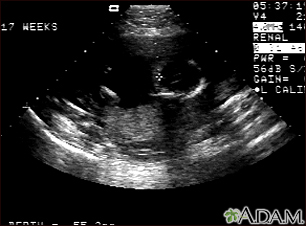

Ultrasound, normal fetus - ventricles of brainBackUltrasound, normal fetus - ventricles of brainThis is a normal fetal ultrasound performed at 17 weeks gestation. The development of the brain and nervous system begins early in fetal development. During an ultrasound, the technician usually looks for the presence of brain ventricles. Ventricles are spaces in the brain that are filled with fluid. In this early ultrasound, the ventricles can be seen as light lines extending through the skull, seen in the upper right side of the image. The cross hair is pointing to the front of the skull, and directly to the right, the lines of the ventricles are visible. E-mail FormEmail ResultsName:Email address:Recipients Name:Recipients address:Message: